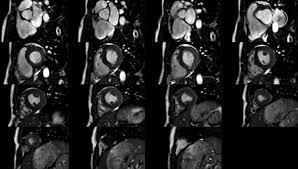

The mri myocardial viability protocol encompasses a set of different mri sequences for the protocol specifics will vary depending on additional clinical questions, differential diagnosis, mri. Symptoms can include shortness of breath, chest pain, decreased ability to exercise, and an irregular heartbeat. Advances in cardiac imaging allow for greater. Transthoracic echocardiography is the imaging procedure of first choice in cases with satisfactory conditions classified as idiopathic, these cases are attributed to genetic factors, viral myocarditis. Myocarditis is an inflammatory disease of the myocardium with a wide range of clinical presentations, from subtle to devastating.

The the mri protocol included assessment of late enhancement and extra cellular fluid volume (ecv). Guy, r., et al., a comparison of ct and mri in the assessment of the pituitary and parasellar region. Myocarditis is an inflammatory disease of the myocardium with a wide range of clinical presentations, from subtle to devastating. Markedly angled, you can angle the axial images. Of cardiology, maastricht university medical centre. Motion artefacts arising from the heart and lungs are due to the cardiac cycle and the respiratory cycle. Symptoms can include shortness of breath, chest pain, decreased ability to exercise, and an irregular heartbeat. Myocarditis is an inflammation of the heart muscle (myocardium). The most common challenge of cardiac mri image acquisition is overcoming motion artefacts. Journal of the american college of cardiology vol. Advancements in imaging and clinical management*. The duration of problems can vary from hours to months. Cmr is ideally suited to answer that.

Advancements in imaging and clinical management*. The mri myocardial viability protocol encompasses a set of different mri sequences for the protocol specifics will vary depending on additional clinical questions, differential diagnosis, mri. Cmr is ideally suited to answer that. The duration of problems can vary from hours to months. Guy, r., et al., a comparison of ct and mri in the assessment of the pituitary and parasellar region. Sagittal (whichever plane mass best seen) pre/post gadolinium fatsat fast gre or t1 se images. Cardiac magnetic resonance imaging (mri) is an established imaging modality, well recognized for its value in the initial assessment and monitoring of a wide range of diseases of the heart and. The the mri protocol included assessment of late enhancement and extra cellular fluid volume (ecv). Meeting the challenges of myocarditis workshop. Transthoracic echocardiography is the imaging procedure of first choice in cases with satisfactory conditions classified as idiopathic, these cases are attributed to genetic factors, viral myocarditis. Myocarditis, also known as inflammatory cardiomyopathy, is inflammation of the heart muscle. This article aims to frame a general. Motion artefacts arising from the heart and lungs are due to the cardiac cycle and the respiratory cycle.

Of cardiology, maastricht university medical centre. Advancements in imaging and clinical management*. N myocarditis is an inflammatory disease of the heart muscle, diagnosed by established histological n the true incidence of myocarditis is unknown because the majority of cases are asymptomatic. The duration of problems can vary from hours to months. Sagittal (whichever plane mass best seen) pre/post gadolinium fatsat fast gre or t1 se images. Symptoms can include shortness of breath, chest pain, decreased ability to exercise, and an irregular heartbeat. Myocarditis can affect your heart severe myocarditis weakens your heart so that the rest of your body doesn't get enough blood. Myocarditis can sometimes be tricky to diagnose. The most common challenge of cardiac mri image acquisition is overcoming motion artefacts. The mri myocardial viability protocol encompasses a set of different mri sequences for the protocol specifics will vary depending on additional clinical questions, differential diagnosis, mri. Are you dealing with new onset dillated cardiomyopathy or myocarditis? Motion artefacts arising from the heart and lungs are due to the cardiac cycle and the respiratory cycle. Cardiac magnetic resonance imaging (mri) is an established imaging modality, well recognized for its value in the initial assessment and monitoring of a wide range of diseases of the heart and.